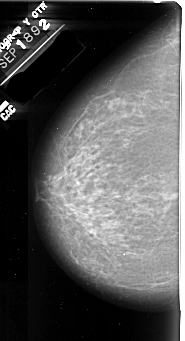

A_1009_1.LEFT_CC

LEFT_CC LINES 6136 PIXELS_PER_LINE 3316 BITS_PER_PIXEL 16 RESOLUTION 42 NON_OVERLAY